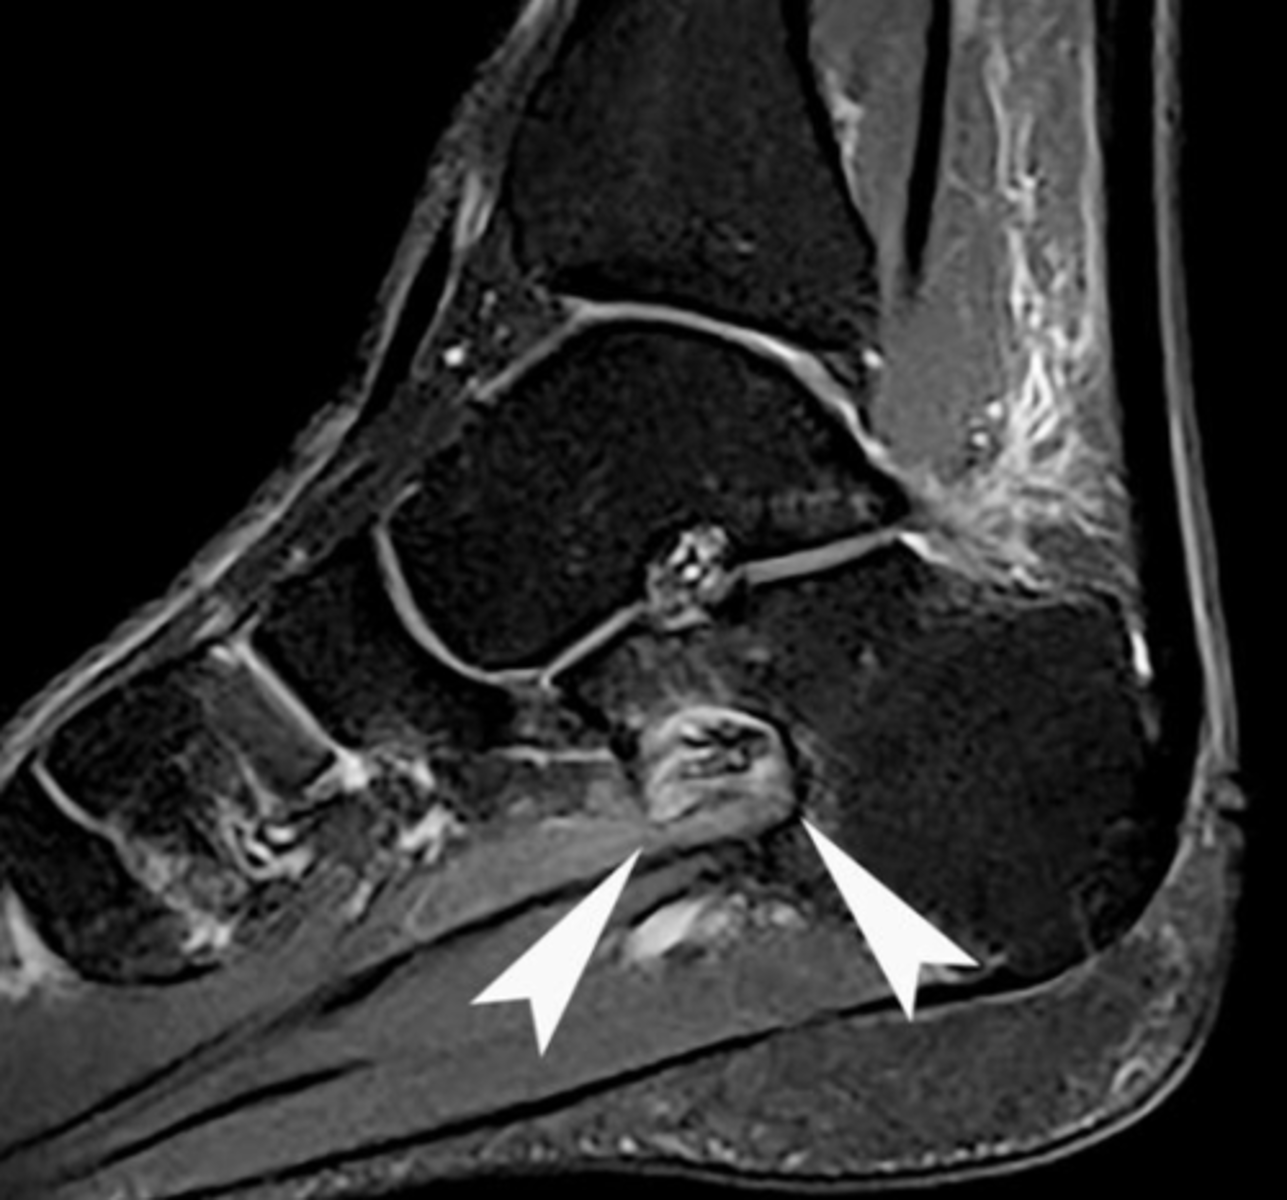

What are the advantages of using MRI for foreign body imaging?

• Very sensitive for soft tissue imaging

• Utilisation of different sequences can assist in FB detection

• 3D reconstruction is available

What are some disadvantages of using MRI for foreign body imaging?

• Most expensive modality

• Must never be used if there is any possibility of a metallic FB

• Claustrophobia

• Safety of patient with unknown foreign body